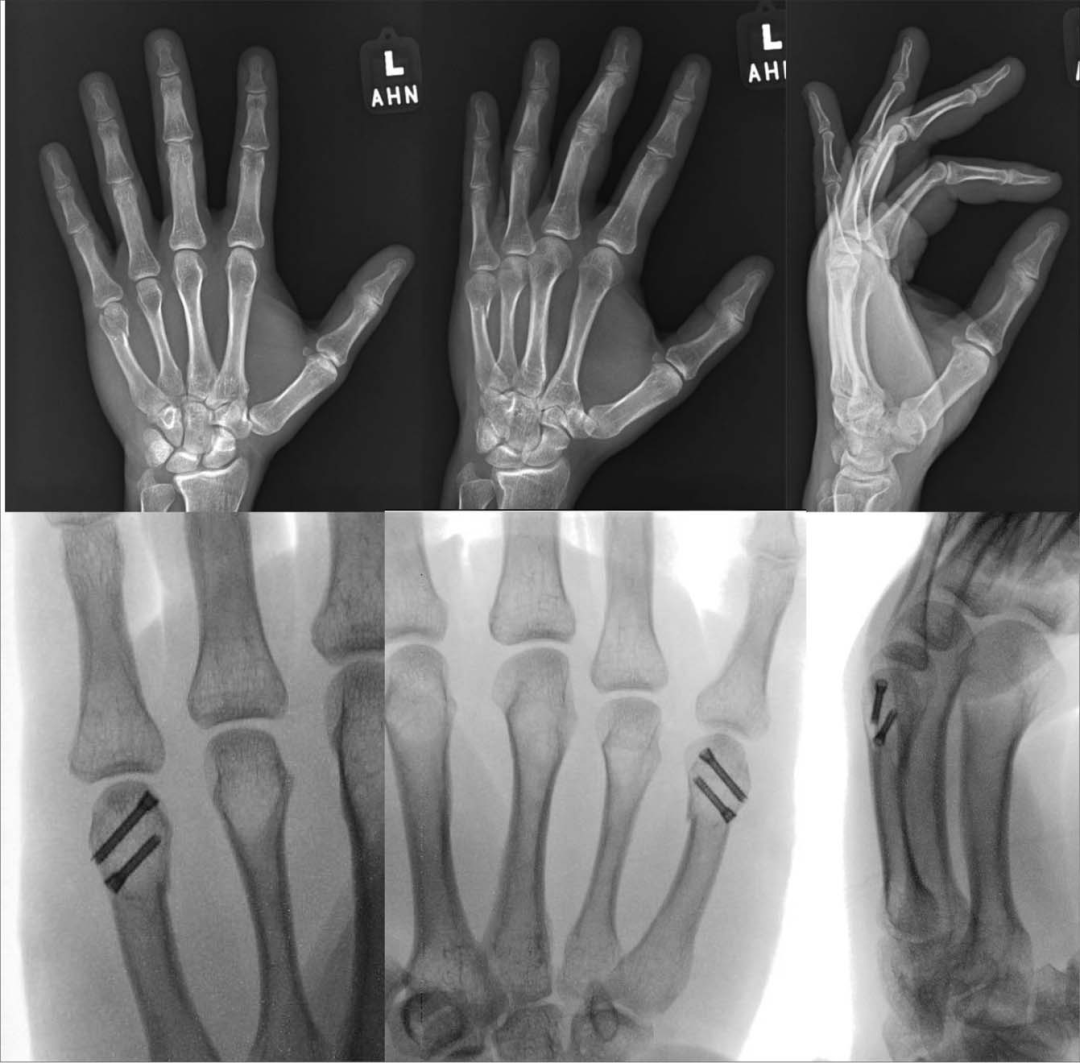

对于累计关节面20%或存在1mm台阶的骨折,建议进行手术治疗,术技术包括经皮穿刺闭合复位、克氏针固定、微型螺钉固定或微型钢板

固定。

对于远端骨量充足的骨折,髓内固定的应用可能是可行的(图2)